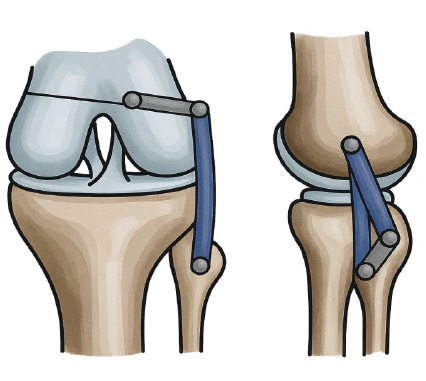

Figure 4: Illustration showing the technique of posterolateral corner reconstruction.

- Anatomic PLC reconstruction: A semitendinosus autograft was harvested through the same incision. Using an anatomical double-bundle reconstruction technique adapted from multi-ligament knee reconstruction principles, tunnels were drilled into the fibular head (to recreate the popliteofibular ligament) and into the lateral femoral condyle (for LCL and popliteus insertion). The graft was passed and tensioned with the knee in 30° of flexion and neutral rotation, then secured with interference screws and cortical fixation buttons as required.